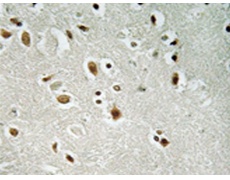

IHC positive control: |

Human brain tissue |

IHC Recommend dilution: |

50-100 |